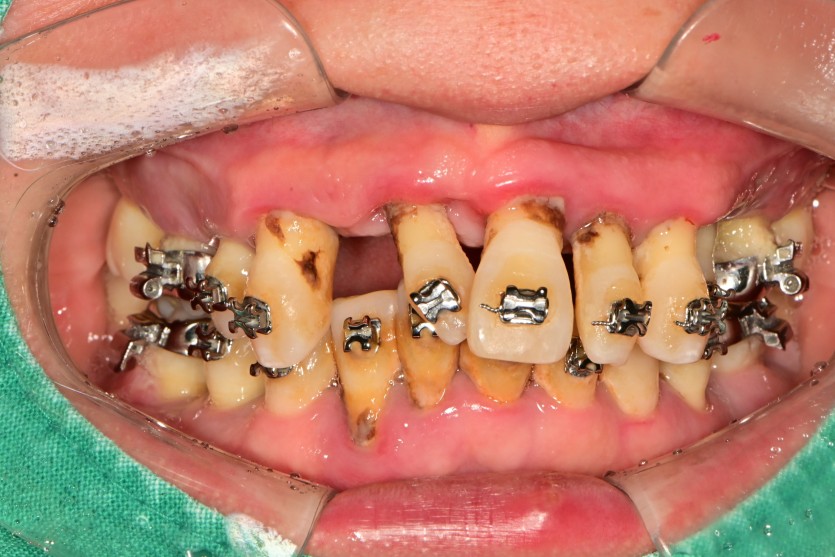

전체 임플란트 증례입니다.

18개의 임플란트로 완성하였습니다.